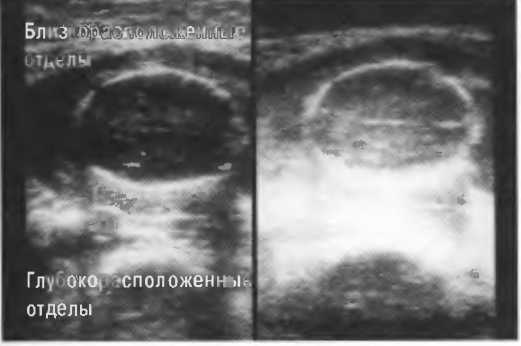

Усиление отраженных ультразвуковых волн ультразвуковой системой. Отраженным сигналам, идущим от глубокорасположенных тканей, необходимо более интенсивное усиление, чем сигналам, поступающим от тканей, расположенных более поверхностно. В соответствии с этим ультразвуковой аппарат снабжен двумя системами контроля чувствительности прибора. Система изменения чувствительности при исследовании близкорасположенных тканей усиливает отраженные зхосигналы от структур, расположенных над точкой фокусировки ультразвукового луча, система изменения чувствительности при |

|

|

исследовании глубокорасположенных тканей усиливает эхосигналы, отраженные от структур, расположенных за точкой фокусировки ультразвукового луча. Эти системы существуют для получения одинаковой эхогенности одних и тех же тканей, но на различной глубине. |

На эхограммах рис. 13 представлены различные варианты регулировки чувствительности и усиления по глубине.

Рис. 13а. Эхография печени. Слева: слишком слабое усиление глубоких отделов. Справа: слишком слабое усиление поверхностных отделов.

Рис.13б. Эхография печени. Слева: общее повышение чувствительности. Справа: общее понижение чувствительности.

Рис.13в. Эхография печени. Слева: слабое усиление срединных отделов печени, справа: правильная регулировка, усиление по глубине.

Рис. 13г. Головка плода. Слева: общая чувствительность слишком высока. Справа: общая чувствительность определена правильно, однако она слишком высока для точного измерения бипариетального диаметра.

Рис. 13д. Общая чувствительность слишком низка для исследования внутренней зхоструктуры, но достаточна для точного измерения бипариетального диаметра.

Рис.13е. Слева: плохая визуализация в результате слишком высокого усиления передних отделов; сравните нечеткое изображение передней части головки с достаточно четким изображением задних отделов (сравните рис. 13ги 13д;. Справа: регулировка по глубине была изменена; теперь определяется слишком низкое усиление близких структур и слишком высокое усиление глубокорасположенных структур.

Можно производить также регулировку чувствительности прибора в зависимости от глубины расположения объекта сканирования (рис. 14д-е).

Рис.14д. Изображения головки плода. Слева: сбалансированное по глубине изображение, общая чувствительность низкая. Справа: чувствительность прибора в ближних отделах сильно завышена; ее необходимо уменьшить, в то время как общая чувствительность должна быть увеличена с тем, чтобы можно было визуализировать всю головку.

Рис. 14е. Слева: хорошо сбалансированное изображение. Справа: чувствительность в глубоких отделах необходимо уменьшить, а в близкорасположенных отделах — увеличить.